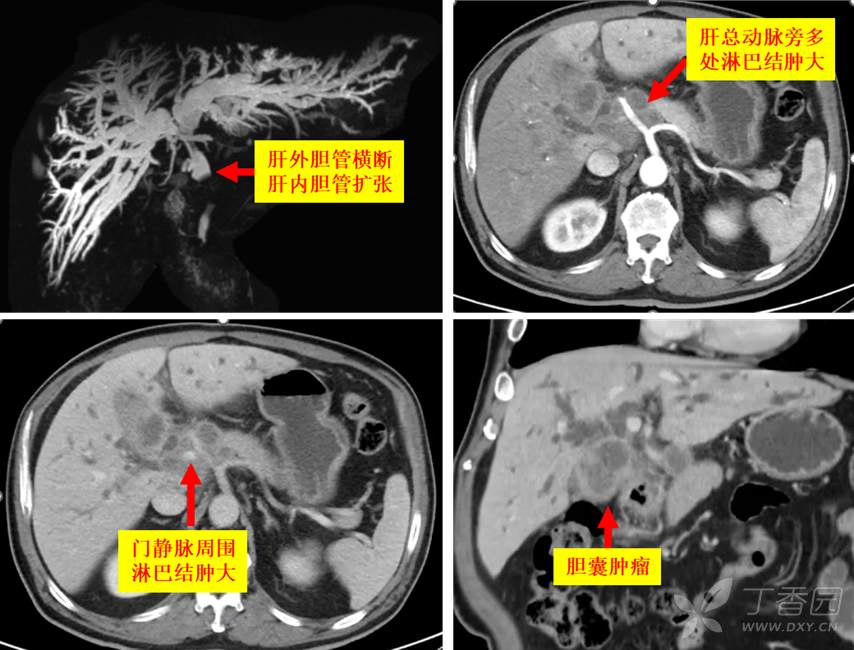

病例二:男性患者,65岁,因上腹胀痛伴梗阻性黄疸,于2022年4月29日当地医院行腹腔镜胆囊造瘘术,术中未取病理。忍不住吐槽:患者术前伴有肿瘤标志物升高,影像已经提示胆囊占位侵及肝脏,居然还按照胆囊结石胆囊炎行腹腔镜胆囊切除,错误!进去发现腔镜下无法完成手术,病理都不取,错上加错!梗黄是肿瘤压迫,或者侵犯胆管造成的,行胆囊造瘘根本于是无补,三重错误!实属不该!术后梗黄丝毫没缓解,反而逐步加重。入院后影像检查如下,肝总动脉和门脉周围都有肿大淋巴结,不排除已被肿瘤浸润可能,同时胆红素超过200,确实无法行根治性手术。于是定下了先减黄,后降期,再行根治性手术的三步走治疗策略。

第一步减黄:穿刺左侧肝管,以便将来根治性手术行右肝切除;将引流管放过胆管狭窄段,说明胆管被压迫可能性较大,受浸润可能性小。

第二步降期:减黄后1个月胆红素降到了50,MDT讨论后制定了靶向+免疫+HAIC治疗策略;后续胆红素进一步降低,第二次HAIC后加用放疗。如下: